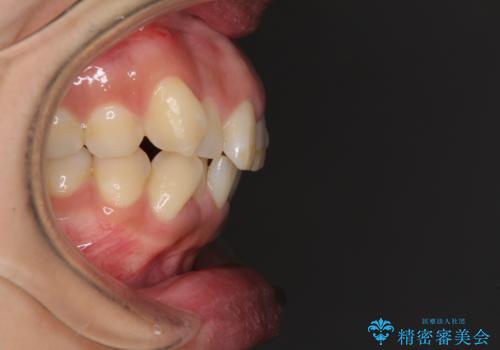

- 上下前歯のデコボコを気にして来院された患者様です。

デコボコが強いため、非抜歯で矯正をすると出っ歯仕上がりとなるため、上下左右の第一小臼歯4本を抜歯することとしました。